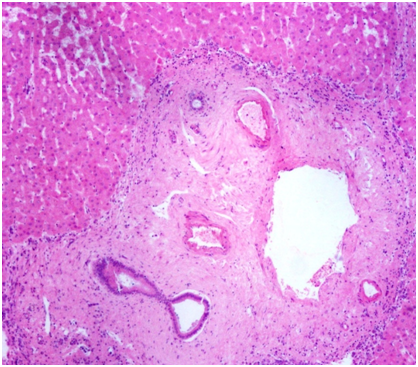

Bernard et al.33 observed that few patients with idiopathic portal hypertension behaved like end-stage liver disease and developed features of decompensation in the form of ascites, jaundice and hepatic encephalopathy during the course of illness. In a subset of patients with NCPH, complications such as acute or chronic liver failure or an end stage liver disease with decompensation,34–39 and hepatopulmonary syndrome are severe enough to warrant a liver transplantation.40,41 We had an opportunity to study, the gross and histology in liver explants (MJ) of 2 (both men) of 57 patients (3.5%) with a pre - transplant diagnosis of cryptogenic cirrhosis but had NCPF in the explant specimen. Grossly, the liver (Figure 1) showed patchy surface nodularity. The cut surface showed vague nodulartity. The capsule was mild thickened. Light microscopy revealed variable portal expansion with dense fibroelastosis; fibrous septa were seen extending from the portal tracts into adjacent lobular parenchyma linking with other portal tracts (portal to portal fibrosis) and the central veins (portal to ventral vein). Crowding of the portal tracts was also appreciated. The portal veins show fibrointimal thickening, medial muscular hypertrophy and narrowed lumen in foci. Few aberrant blood vessels immediately adjacent to the peripheral portal tracts are noted. Obliterated portal veins with increased portal vascularity was also noted. The lobular parenchyma showed patchy macrovesicular steatosis along with mild ballooning and sinusoidal dilatation. The central vein also showed thickening of the wall in foci. Nodular regenerative hyperplasia was also noted (Figure 2). Thus features of NCPF were noted in both the liver explants of “cryptogenic cirrhosis” cases.

Figure 2 Light microscopy displaying dense portal fibrosis with portal vein thickening and luminal narrowing.